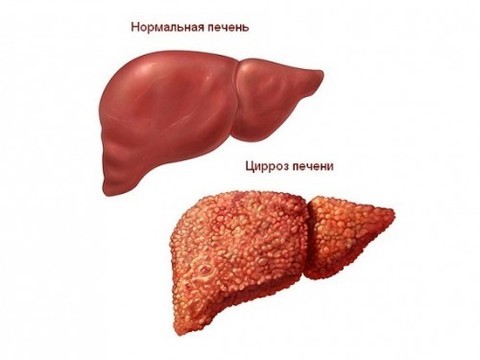

Изображения заболеваний печени: признаки и симптомы

Раздел: Пульс времени